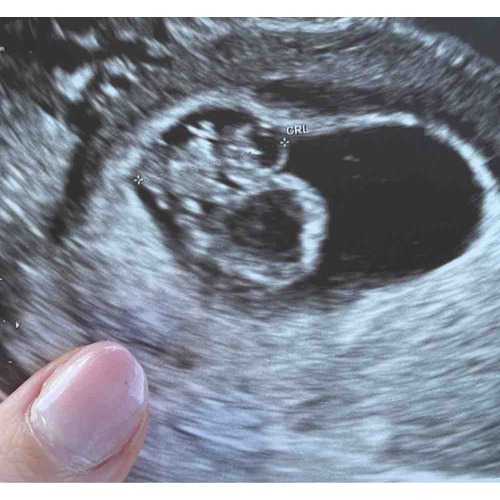

Hé, ik heb ook een poliep maar wel in mijn baarmoeder zelf. Ik heb er zelf geen last van maar schrok wel met de eerste echo. (7w)

Na de tweede echo (8+4) wel geruster op hoor. De gynae zei dat het kindje goed gegroeid was en dat het niet veel last heeft van de poliep. Poliep is ook niet doorbloed dus kan in principe ook geen ‘voeding’ afnemen van het kindje. Ik mag wel nog een extra echo op 12 weken als tweede opinie in Leuven. Dan zijn ze helemaal zeker dat het niet voor problemen kan zorgen! Helemaal links zie je de baby (met armpjes uitsteken) en net rechts ervan de poliep!